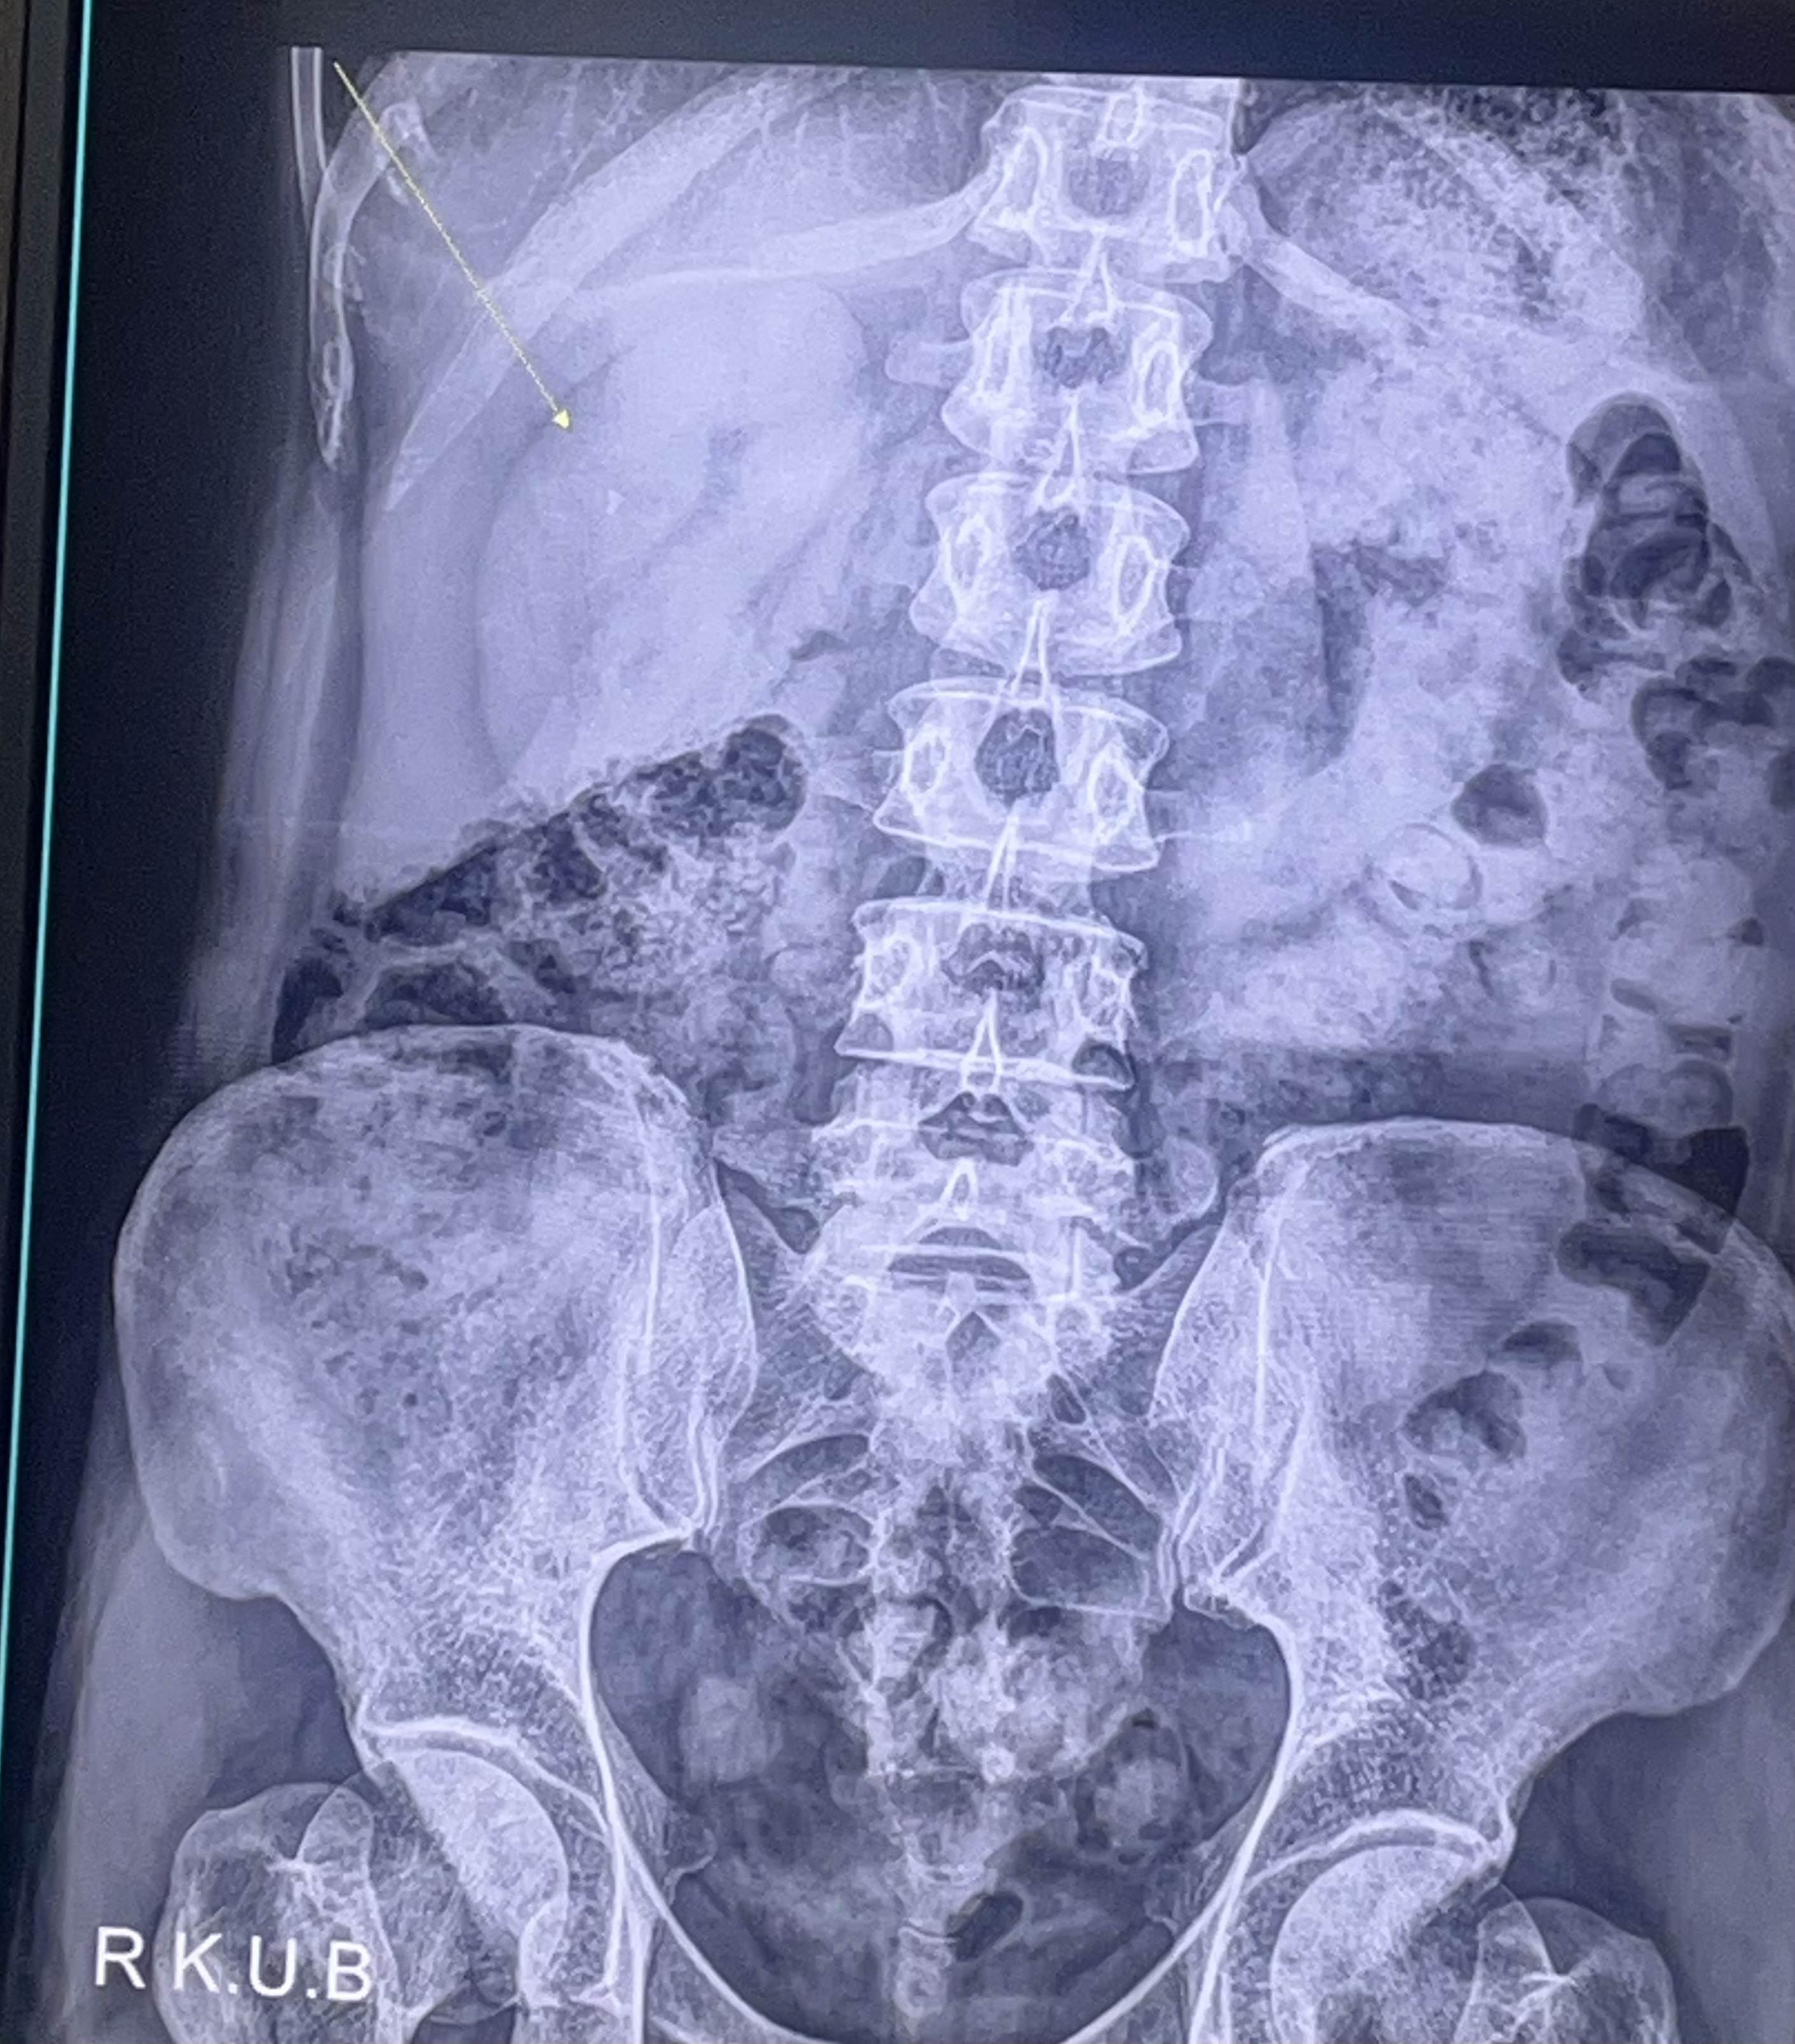

[잡담] G식백과) 요로결석 5밀리면 얼마나 심각한거임? [10]

저걸 살아있네? 하는 수준이지 내가 요로결석 걸려봐서 알아

엄지 손톱 길이 절반만한게 요도로 나오는거임

자연배출 될 확률 5할이 안된다네

0.5cm니까 손톱의 반정도?

모루겠지만 겁나 아플꺼야… 나 신장결석으로 얼마전에 깸. 저게 한 3~4미리 쯤 되어 보이는데

난 2mm 짜리라 병원에서 진통제 맞고, 물 많이 먹어서 자연 배출 됐는데 5mm면 답 없어

꺼츄로 길고 단단한 응기잇봉 집어넣고 레이저 쏴서 빼야 할 레벨 같은데 그 정도면